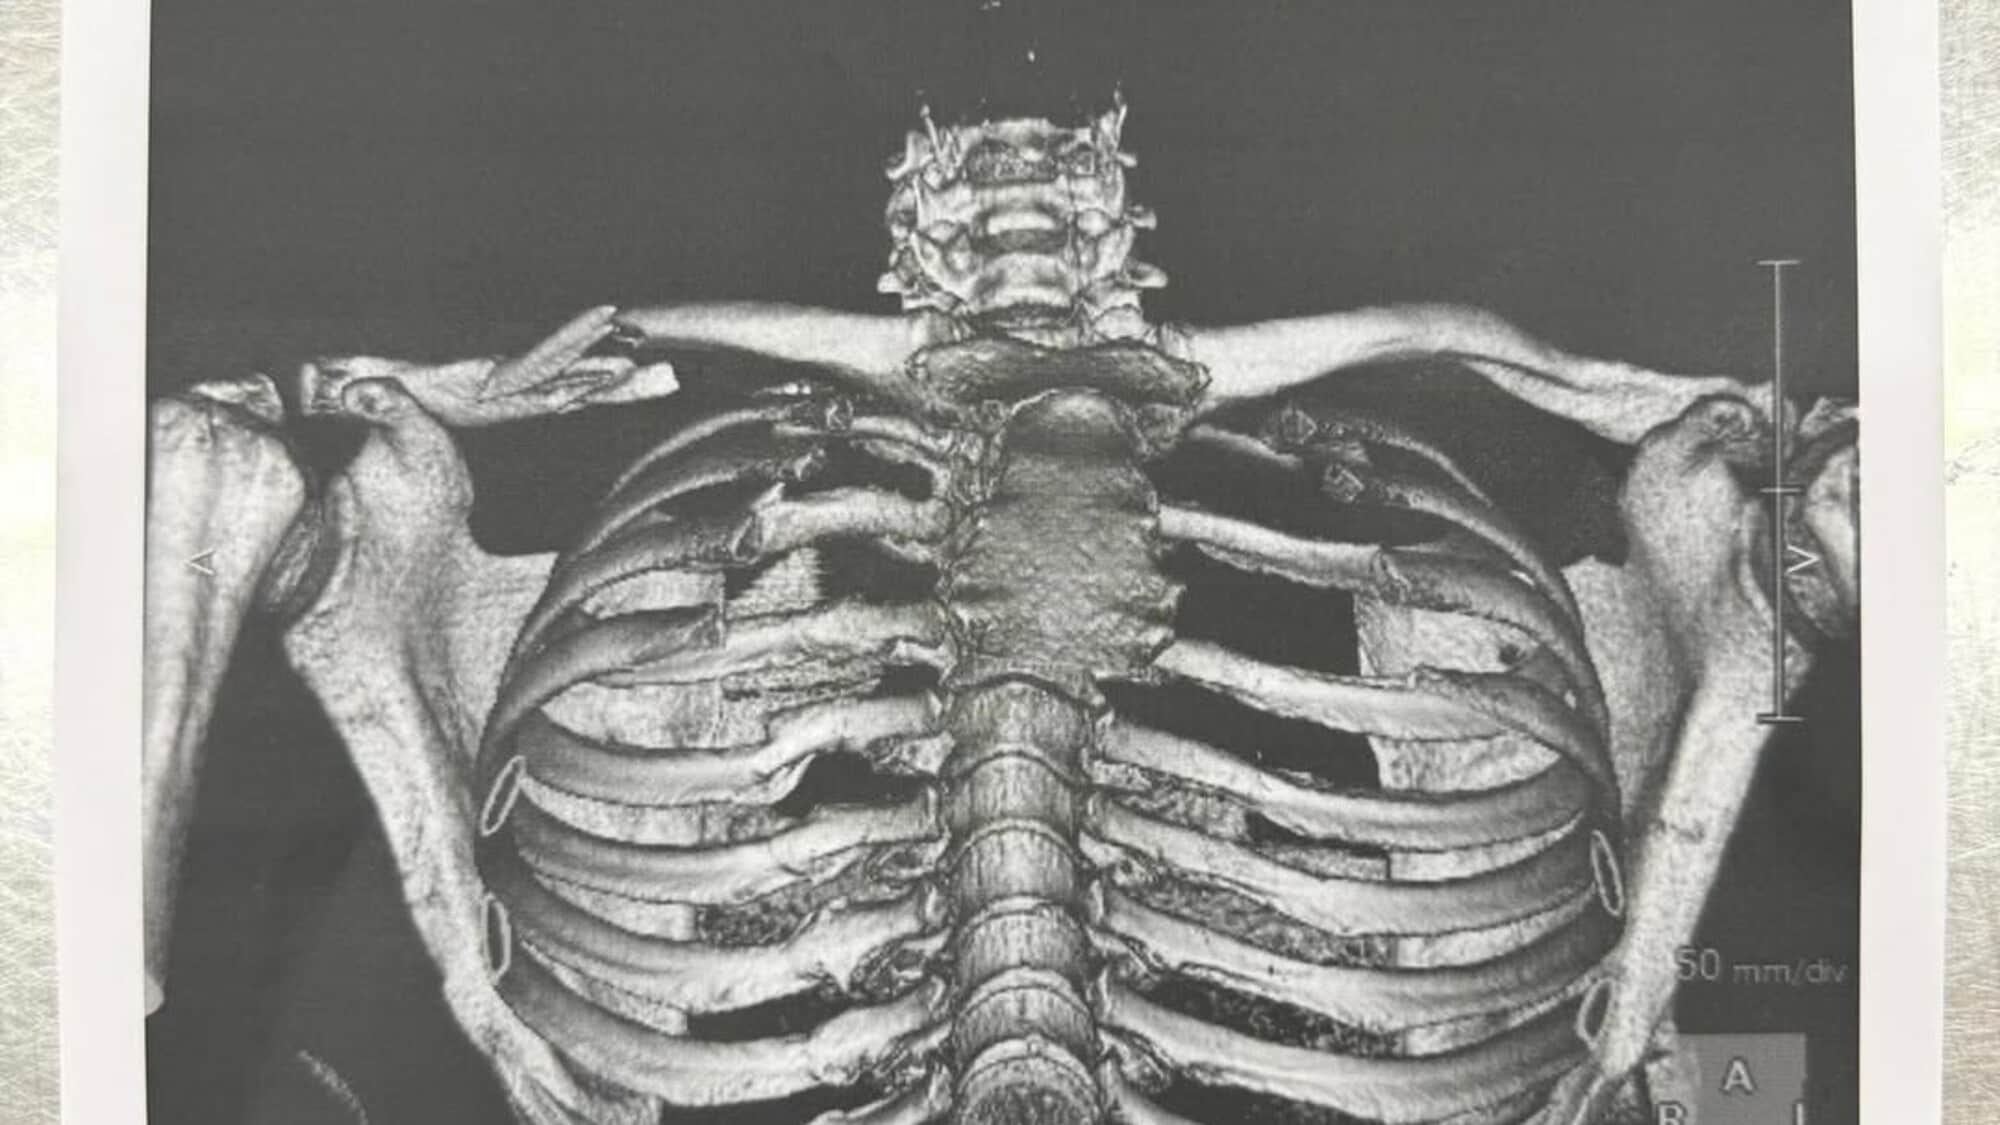

Il 2025 è, nel complesso, un’annata complicata per Jorge Martin, caratterizzata da diversi infortuni. In Giappone, infatti, ne ha rimediato un altro. A seguito di un errore al via della Sprint, lo spagnolo ha lasciato la pista con una frattura scomposta della clavicola destra e per questo è già volato in Spagna per essere operato.

Proprio mentre ieri stava tornando a casa, ha condiviso un post sui suoi social. Ha messo foto delle sue condizioni dopo la caduta, di lui trasportato in elicottero in ospedale e della sua lastra in cui si vede chiaramente il danno rimediato. A corniciare le tre foto, le sue parole: “Fa male... ma è questo è ciò che sono. Non mi vedrete mai mollare tutto. A presto!”